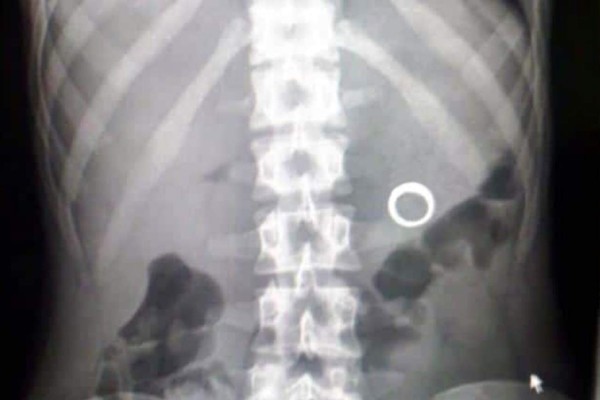

'En una radiografía (que se le tomó) salen los elementos dentro del abdomen', apuntó. La mujer, en tanto, sufrió 'laceraciones' en las orejas.

Los aretes serán usados como prueba contra el delincuente.